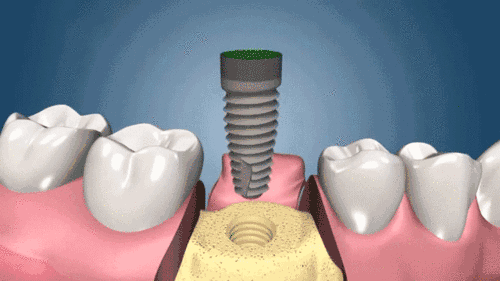

種植牙動(dòng)圖

二、種植手術(shù),醫(yī)生會(huì)根據(jù)不同顧客做出術(shù)前種植方案設(shè)計(jì),采用手術(shù)將種植體植入牙槽骨內(nèi),種一顆種植體很快大約用10-20分鐘。